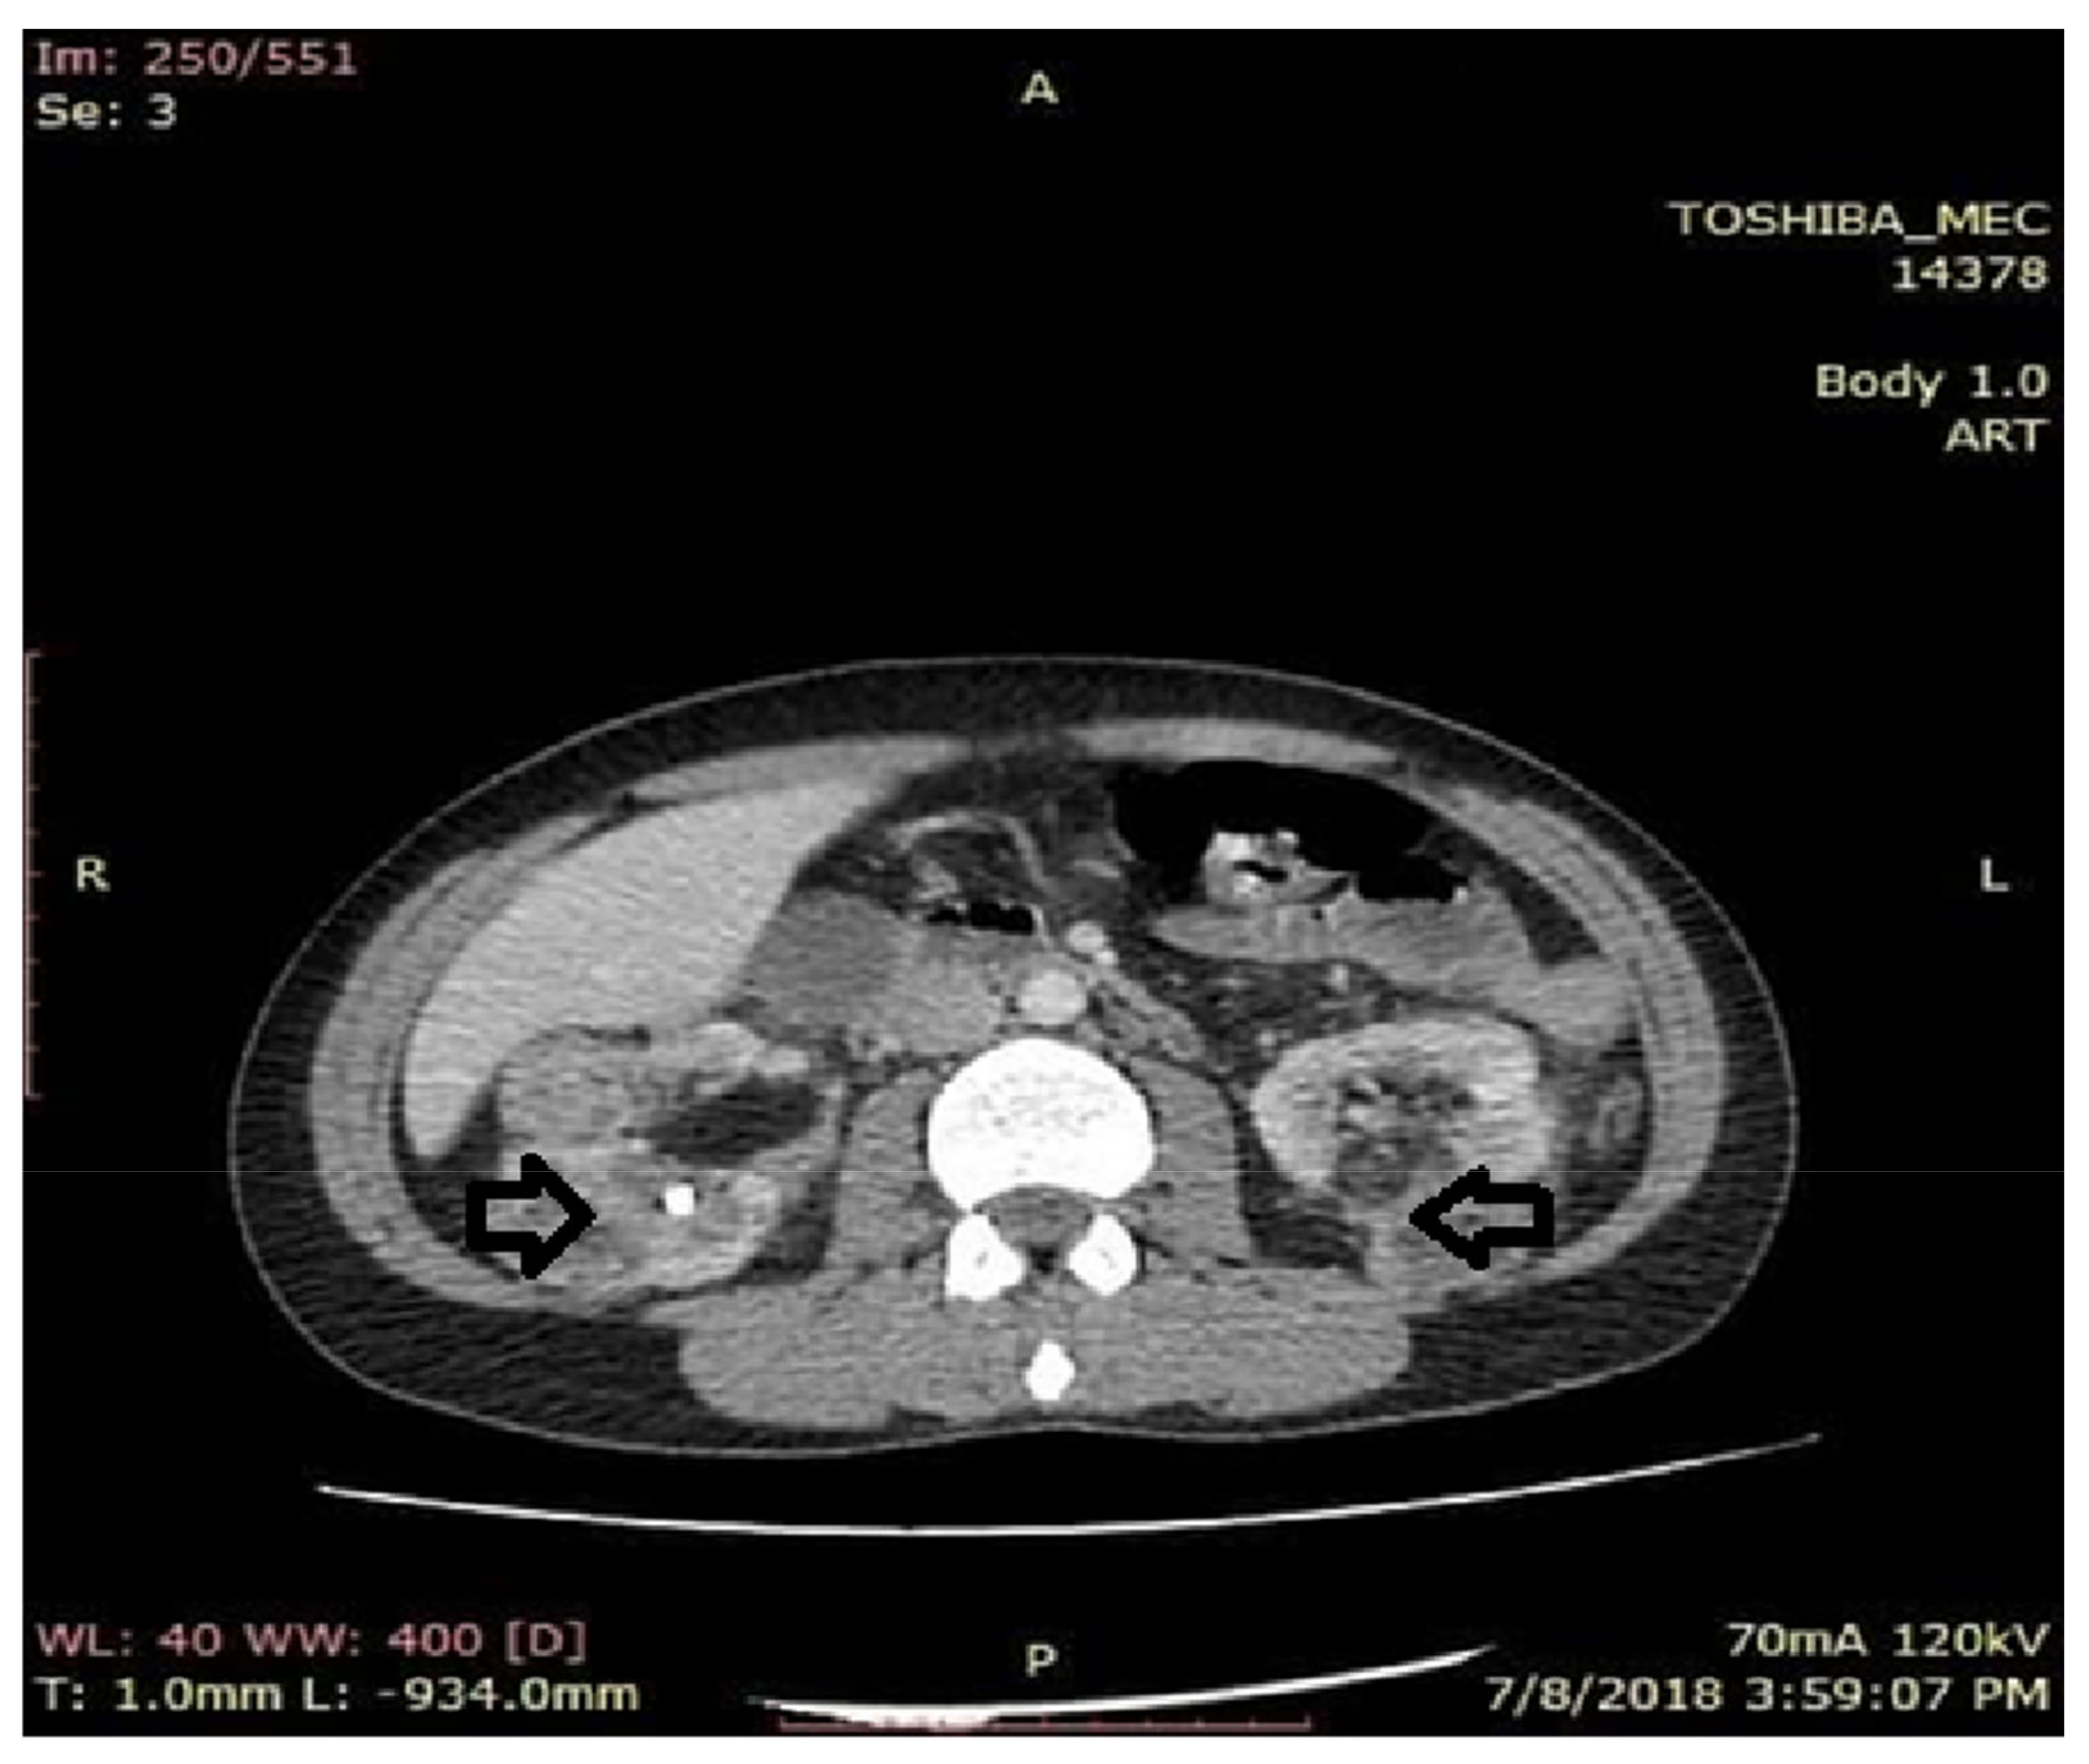

Figure 5.

Axial computer tomography (CT) section with contrast substance. Kidneys with alteration of the physiological architecture with erasure of the cortico-medullary differentiation, by the presence on the entire bilateral renal surface of round oval formations, diffusely contoured with mixed component. The CT appearance pleads for angiomyolipomas.